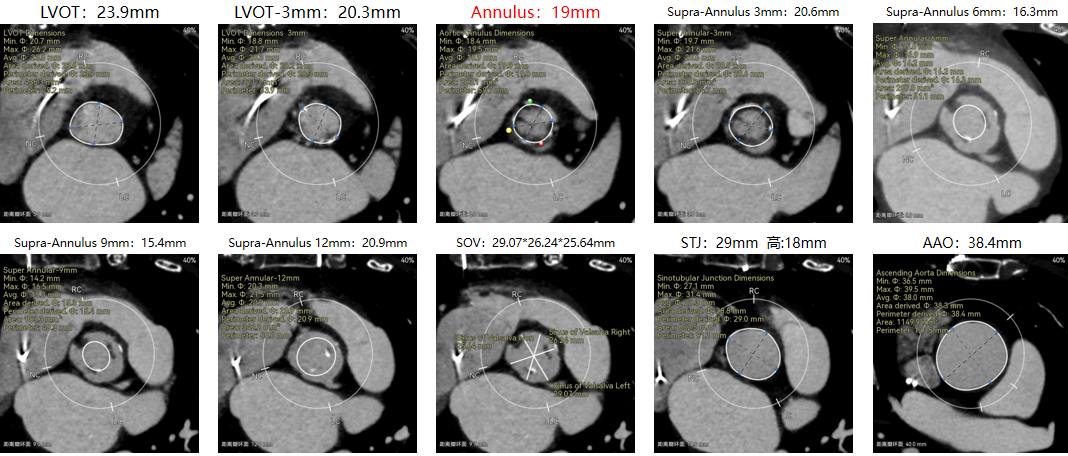

修建成教授 南方医科大学南方医院(点击查看专家详细简历) 直面瓣膜衰败,选对每一步护心路:前不久的ESC会议重磅发布瓣膜指南更新,将TAVR的患者年龄下调到70岁,且整体治疗理念迈向终身管理。该患者经历过一次外科手术,在人生70岁的当口,因生物瓣衰败再度面临 “心” 之困境,选择总是人生的一个重要课题,患者需要更微创的疗法、更耐久的瓣膜,医学的进步都是在主动探索中往前推进的,我们遵从患者的选择,不再被动应对衰败,而是主动定义瓣膜生命周期的边界。 手术一切按照既定的预演完成,术后患者情况良好,这不仅是一台手术的成功,更是将复杂瓣膜治疗推向 “精准化、耐久化” 新境序章,从瓣膜释放的瞬时血流动力学到远期抗钙化性能的预判,每一个参数都在诉说对长效生存的敬畏! 崔凯教授 南方医科大学南方医院(点击查看专家详细简历) 万千临床难题,唯提纲挈领方得始终:生物瓣衰败、心脏腔室小,这些问题都给手术添了不少难点。我始终觉得,需根据患者情况定手术方案,选择最合适的器械,综合考量:全新上市的预装干瓣开启了瓣膜心时代,预装技术让瓣膜装配标准化,规避了装载可能存在的肉眼不可见的损伤,干式储存技术规避了传统湿瓣的储存条件的钙化源头。可以说,为瓣膜的耐久性本身又增添了砝码。 对于衰败后的70岁患者,需要考量其长期耐久性问题,全新的产品需提前熟悉其产品特性;实践创新是心里装着对生命的敬畏,才能在复杂手术里找到办法。手术刀处理的不只是病,更是在跟时间赛跑,帮患者找希望。我们始终在找能让患者长期好好活下去的最好办法! 患者病史 现病史:患者近1月余前开始出现活动后胸闷、气促,爬楼、快走即可出现,休息后数分钟可缓解,至我院查心脏超声,提示:主动脉瓣生物瓣置换术后;主动脉瓣位生物瓣前向血流速度增快;左房增大,室间隔与左室后壁增厚,左室舒张功能降低,右房、右室内起博器电极线存留,二尖瓣返流轻中度,三尖瓣返流轻中度,肺动脉高压,心包积液(微量) 既往史:平素身体一般,有高血压1年,规律服用氨氯地平降压,有风湿性心脏病史,2011年行主动脉瓣生物瓣置换术;2011年植入双枪起搏器,2019年更换起搏器电池 超声提示: 主动脉瓣生物瓣置换术后;主动脉瓣位生物瓣前向血流速度增快,提示狭窄 左房增大,室间隔增厚,升主动脉增宽 右房、右室内起搏器电极线存留 三尖瓣反流(中度)二尖瓣反流(轻度) 肺动脉高压 左室射血分数正常 术前CT 生物瓣衰败ViV,原瓣膜内径19mm,LVOT23.9mm,靠原有框架锚定; 双侧冠脉开口高度可,窦部空间较大,VTC-SIMU:4.68,无冠脉风险;心脏角度47.2°; 心腔内径较小,心室壁无明显增厚,术中有循环崩溃可能; 右侧髂总动脉处有散在钙化,外周双侧入路无明显迂曲,双侧内径可,低分叉,主动脉弓距弓角条件良好; 手术策略:推荐右侧股动脉为主入路;生物瓣衰败ViV;球囊不预扩,22mm球囊后扩,预装可回收AV23主动脉瓣膜,瓣下5mm初始定位释放,工作位充分评估,符合释放要求后无张力释放 手术过程 最终造影 术后即刻探查超声平均跨瓣压差10mmHg。 术后患者当天下地,48小时出院 Prostyle A®预装干瓣——助力临床最优化解决方案: 1.平衡收腰:该患者生物瓣环较小,瓣膜型号需计算精准,Prostyle A 23号瓣膜平衡的收腰设计,兼顾血流动力学与冠脉安全; 2.柔顺过弓:较细的输送器尺寸+亲水涂层,在入路存在钙化的情况下,也能安全通过,过弓顺利,显著降低了血管并发症风险; 3.预装干瓣 便捷顺安:金仕生物专利抗钙化技术运用纳米技术去除组织内的细胞碎片和磷脂,封闭游离醛基,从根本上阻断了瓣膜钙化的多项因素,显著提升了瓣膜的耐久性;同时,相比较传统戊二醛保存方式,干式存储最大限度的保留心包的亲水亲油平衡,还原组织天然曲柔性,进一步保障了瓣叶开合,保证长期耐久性; · END ·